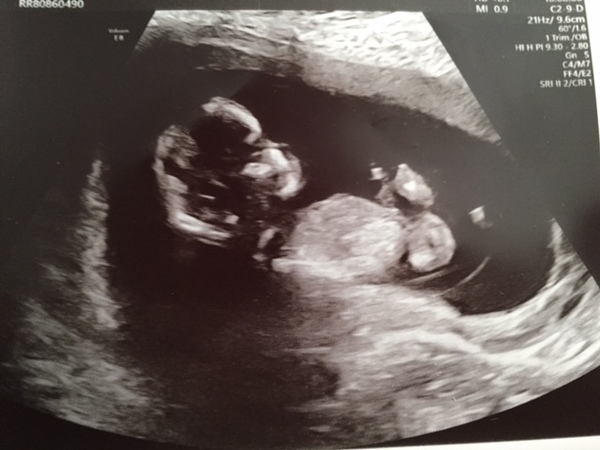

Pumpkin2018 · 26/04/2018 15:53

Congratulations to all who had positive scans today.

I also had mine today, I have one very active, wriggling baby.

Measured a little further on than expected and my due date is now 29th October.

Congratulations @Pumpkin2018! Another lovely picture!

Some very clear scans today ladies!

So glad to hear of the great scans! I had mine today, was ready for the worst as I've had some pains the past few days. But the lazy lump is all good and well. Baby was wriggling for about 3 seconds before deciding now was a great time for a snooze and wouldn't wake up no matter how many jabs it took. Takes after his dad Grin

Beautiful scan picture,@Mayah! Congratulations!

It’s so nice seeing everyone’s scans Smile

So exciting to see all the lovely scans Smile

Here's mine again - but with name and DOB removed now.... doh!! Blush I think he/she looks so petite (I know it's actually tiny I'm not crazy I promise!)